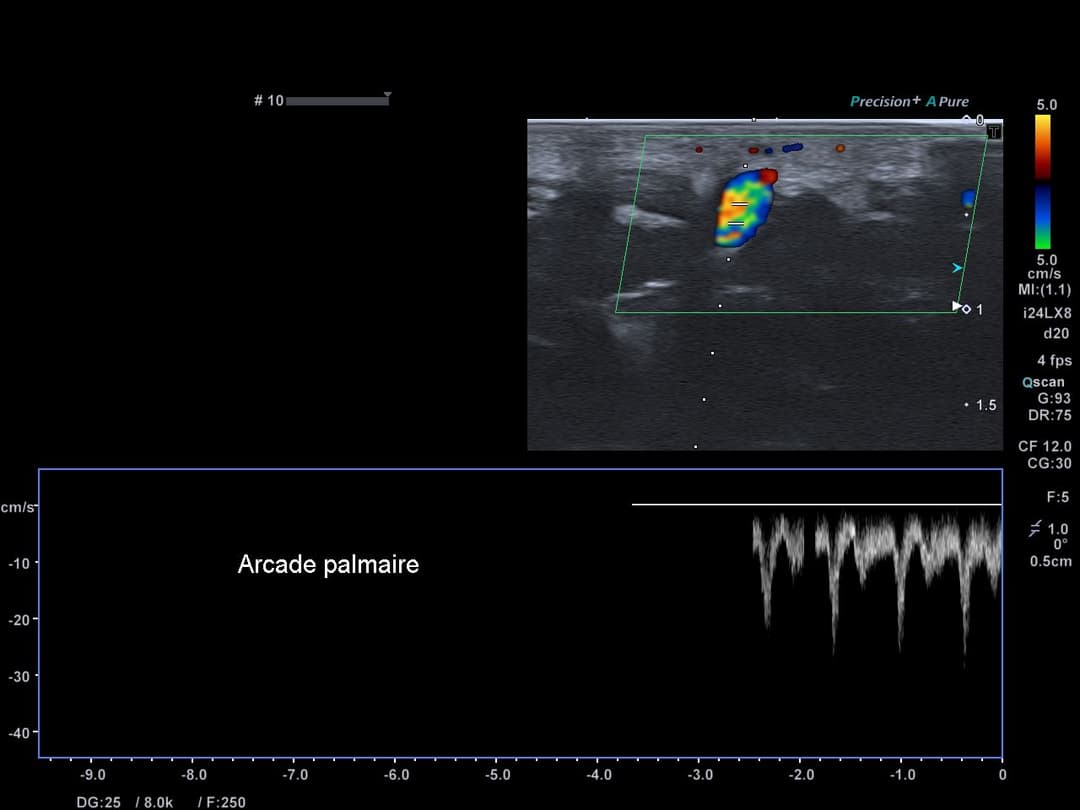

Bonne perméabilité de l'artère radiale, ulnaire et de l'arcade palmaire.